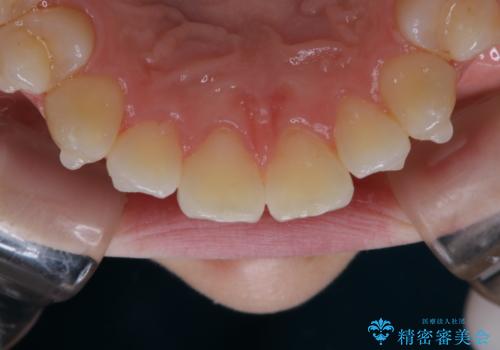

アタッチメント周囲のステインOFFをPMTC で

- インビザライン矯正治療中に、アタッチメント周囲のステインが気になるとのことでした。PMTC30分コースを行いました。

マウスピース矯正インビザライン治療では、歯の表面にアタッチメントという突起を設定します。(アタッチメントは歯の動きを効率的に移動するためのものです)

アタッチメントが歯に付くと、表面が凸凹し磨き残しが多くなったりと、プラークや歯石・着色がつきやすくなることがあります。

矯正治療中もPMTCを定期的に行い、専門的な機械でしっかりと汚れを除去することがおススメです。